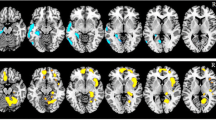

The18F-FDG PET images were co-registered with the MPRAGE images, and then segmented into the six subfields (Fig. 1). Their volumes and the SUVs were calculated individually. The detail methods were described in the “Supplementary materials”.

Asymmetrical volume and metabolic changes in the thalamic subnuclei in both TLE cases

Morphologically, the ipsilateral entire thalamus showed a significantly smaller volume compared with the volume of the contralateral thalamus in both TLE cases. Comparison between the volumes of thalamic subregions on both sides in patients with L-TLE (Table 2) showed that only the anterior (p = 0.042) and posterior (p = 0.015) nuclei were significantly smaller on the ipsilateral side. Metabolically, the SUVR were significantly decreased in the ipsilateral intralaminar (p = 0.001), medial (p = 0.007), and posterior (p = 0.001) subnuclei.

In patients with R-TLE, there was no significant volume asymmetry in the thalamic subregions (Table 3). However, PET imaging demonstrated significantly lower SUVs mainly in the anterior nucleus (p = 0.016), followed by the posterior (p = 0.031) and medial (p = 0.043) subnuclei. In both TLE cases, the entire thalamus showed a significant decrease in both total volumes and SUVR ipsilaterally.

Metabolically, the ipsilateral medial and posterior thalamic subregions exhibited more significant hypometabolism in both our TLE cases. The mediodorsal nucleus is an important component of the medial thalamic subregion, connecting to the prefrontal and temporal cortexes in the diffusion imaging study1. Previous electrophysiological studies have demonstrated that the mediodorsal nucleus is involved in the seizure onset of the medial temporal lobe8, participating in the spread of seizures36. Therefore, seizure activity results in prominently lower metabolism in the ipsilateral medio-posterior thalamic subregion in our both L-TLE and R-TLE, which might be related to their dense connections to temporal lobes. This phenomenon could be used as a biomarker to assist in lateralizing the epileptogenic hippocampus. Furthermore, there are still some distinguishing characters of metabolic asymmetry. Patients with L-TLE showed an additional SUVR asymmetry in intralaminar subregion, whereas R-TLE had additionally relatively decreased SUVR in the ipsilateral anterior nucleus. This indicates that differential thalamic neurons are injured in cases of R-TLE and L-TLE, resulting in different metabolic networks.